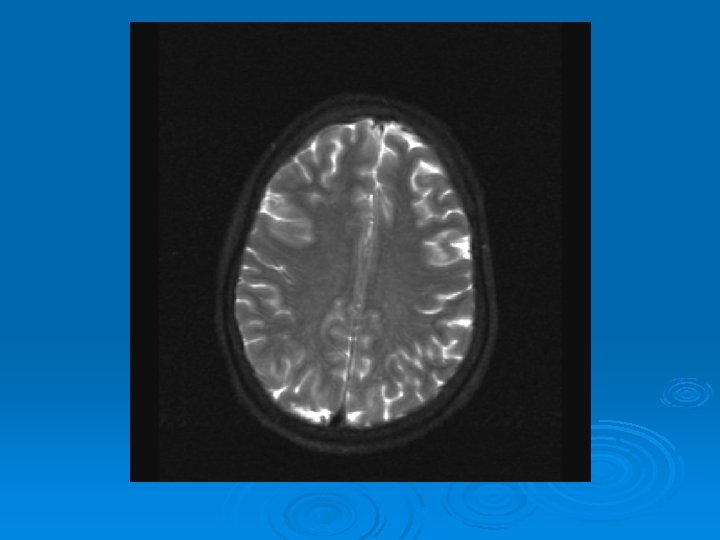

MRI: 2/9/2007 Ø 1. Leptomeningeal enhancement, most prominently seen over the posterior parietal and occipital lobes.

CMV: Ventriculoencephalitis Ø Clinical: Can have abrupt presentation of confusion, apathy, impaired memory, withdrawal, nystagmus, motor weakness, cranial nerve deficits, ataxia, seizures, coma. Can rapidly progress. Ø Labs: CSF: Monocytic Pleocytosis, Low Glucose CMV PCR Positive in CSF: (Sensitivity, Specifity 80, 90%, PPV, NPV, 86 -92, 9598%) Serum CMV viremia Ø Ø Ø MRI: Subependymal enhancement, diffuse hyperintense T 2 WI, ventriculomegaly.

MRI of CMV patient Magnetic resonance images of a patient with cytomegalovirus ventriculitis Ependymal enhancement after injection of gadolinium. DPTA seen on coronal T 1 -weighted image. Ø Highly abnormal ependmal signal on proton densityweighted image of the brain in axial section. Ø Ø See images in: l Arribas et al, Cytomegalovirus Encephalitis, Annals of Internal Medicine, 1996, Vol 125, Issue 7